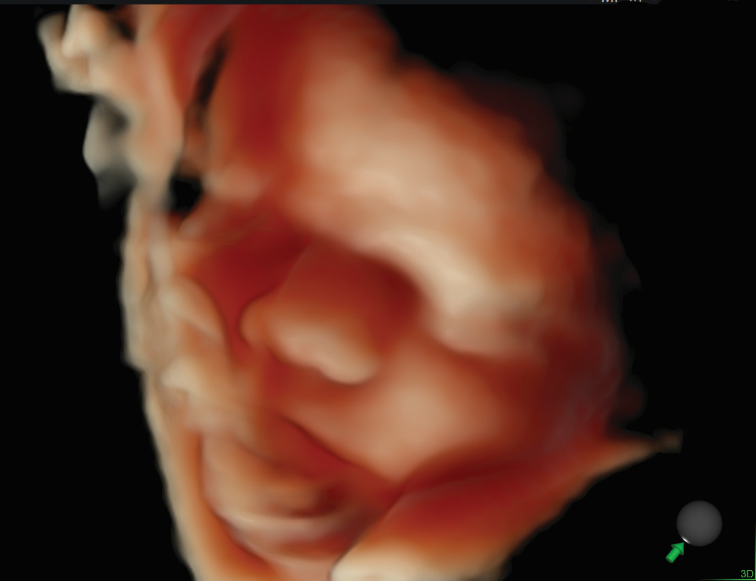

1、胎儿及胎儿附属器的异常检查更卓越

用于胎儿颜面部、 中枢系统及脊柱异常的显示, 通过细致的多切面成像分析胎儿的解剖结构及发育状况。